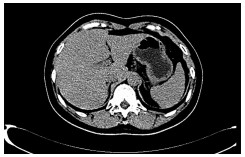

高原地区体外肝切除联合自体肝移植术治疗晚期肝泡型包虫病的术后并发症及其防治策略

摘要(1294) HTML (489) PDF (3321KB)(54)

摘要:

目的  探讨高原地区体外肝切除联合自体肝移植术治疗终末期肝泡型包虫病的术后并发症并探讨防治策略。  方法  收集青海省人民医院2013年1月— 2019年3月接受自体肝移植术的11例终末期肝泡型包虫病患者的手术资料及随访资料,对术中及术后情况进行分析。  结果  11例患者均成功行自体肝移植术,无术中死亡,其中2例(18.18%)行半离体肝切除,9例(81.82%)行全离体肝切除。肝后下腔静脉重建方式中,采用自体大隐静脉进行重建者2例(18.18%),采用人造血管重建者4例(36.36%),5例(45.45%)保留自体肝后下腔静脉。胆道重建方式中,8例(72.73%)行胆肠吻合术,3例(27.27%)行胆管端端吻合术。11例患者的术后并发症主要有出血2例(18.18%);胆汁漏、腹腔感染4例(36.36%),胆肠吻合口狭窄1例(9.09%), 血栓2例(18.18%),肺部感染、胸腔积液2例(18.18%);包虫复发1例(9.09%)。11例患者发生围术期死亡2例(18.18%),其余9例(81.82%)患者均好转出院。  结论  出血、胆道并发症和感染是造成高原地区自体肝移植患者死亡的主要原因,精准把握手术适应证、术前仔细多学科评估、术中精湛的操作、外科技术流程的标准化及精细的围术期管理是降低自体肝移植术围术期病死率、避免和减少术后并发症以及使患者获得长期良好生存的关键。